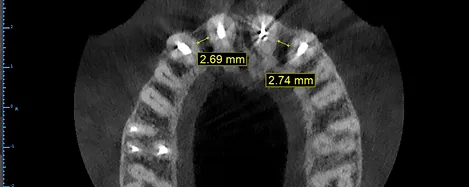

Ao solicitar uma tomografia da região para planejarmos a cirurgia dos implantes percebemos que as raizes dos dentes vizinhos estavam inclinadas impossibilitando a instalanão do implante mais estreito que existe no mercado. A partir daí tínhamos 2 opções:

Tratamento ortodôntico prévio para abrir espaço para posterior instalação dos implantes nas regiões dos incisivos laterais;

Repetir o trabalho em 2 pontes fixas.

A opçao 1 teria como principal vantagem separar todos os 6 dentes. Se em algum momento um desses dentes falhar (quebrar uma lasca ou infiltrar) só precisaríamos trocar esse dente. Para isso iriamos precisar de um Tratamento Ortodôntico prévio e da cirurgia para instalação dos implantes.